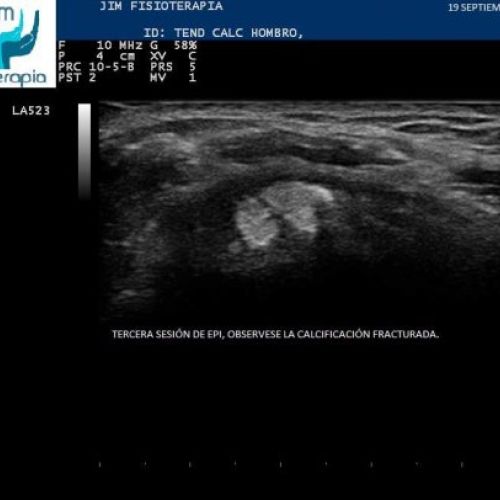

Tratamiento con EPI® de Tendinosis Calcificada del Supraespinoso

Imágenes del tratamiento de un caso de Tendinosis Calcificada del Supraespinoso mediante la terapia EPI® en Madrid.